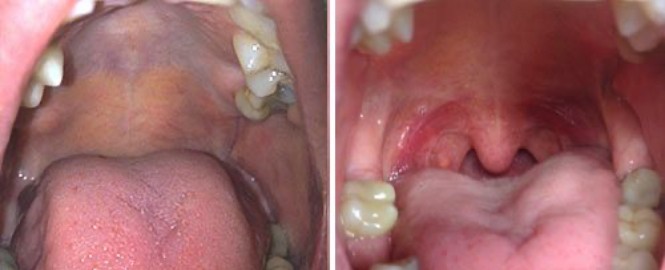

เลเซอร์ลดนอนกรนและภาวะหยุดหายใจขณะหลับ

Courtesy of: Jaana Sippus Hannele, DDS, M.Sc.

Laser source: Fractional Er:YAG

การนอนกรนเกิดจาก ทางเดินหายใจแคบลง โดยเฉพาะเนื้อเยื่อเพดานอ่อนและลิ้นไก่ที่หย่อน ทำให้เกิดเสียงสั่นสะเทือน และอาจนำไปสู่ ภาวะหยุดหายใจขณะหลับ (Sleep Apnea)

เลเซอร์ Er:YAG จะถูกยิงอย่างแม่นยำในบริเวณเพดานอ่อน ลิ้นไก่ และโคนลิ้น ความร้อนจะช่วยกระตุ้นคอลลาเจนให้เนื้อเยื่อตึงขึ้น ทำให้ทางเดินหายใจกว้างขึ้น และเสียงกรนลดลงอย่างชัดเจน